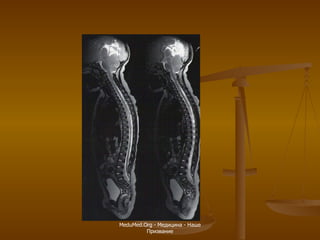

МРТ шейного отдела позвоночника Продолговатый мозг Спинной мозг Второй шейный позвонок Межпозвонковый диск Тело пятого позвонка Остистый отросток Мозжечок Первый шейный позвонок

MeduMed.Org -  Медицина - Наше Призвание

МРТ пояснично-крестцового отдела позвоночника Крестец Пятый поясничный позвонок Межпозвонковый диск (пульпозное ядро) Спинной мозг Конский хвост Копчик Остистый отросток Межпозвонковый диск (фиброзное кольцо)

МРТ пояснично-крестцового отдела позвоночника Миелография Аксиальная плоскость Позвоночный канал Остистый отросток Фасеточный сустав Межпозвонковый диск Позвоночный канал Конский хвост